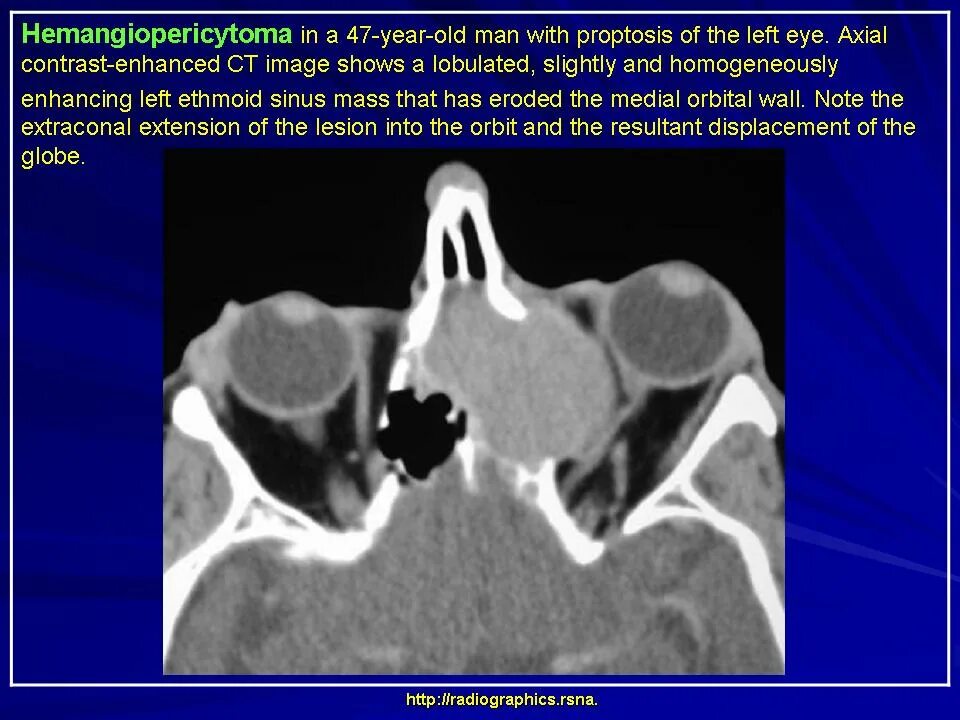

Данные кт